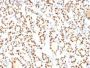

Positive Control

MAD109, MLE-15, H441-4, or H345 cells. Normal thyroid or lung.

Antibody target cellular localization

Nucleus

Tumor expression

Lung cancer|Thyroid cancer

IHC (FFPE) (verified)

Higher concentration may be required for direct detection using primary antibody conjugates than for indirect detection with secondary antibody|Immunofluorescence: 0.5-1 ug/mL|Immunohistology formalin-fixed 0.5-1 ug/mL|Staining of formalin-fixed tissues requires boiling tissue sections in 10 mM citrate buffer, pH 6.0, for 10-20 min followed by cooling at RT for 20 minutes|Flow Cytometry 0.5-1 ug/million cells/0.1 mL|Predicted to show broad species reactivity|Optimal dilution for a specific application should be determined by user